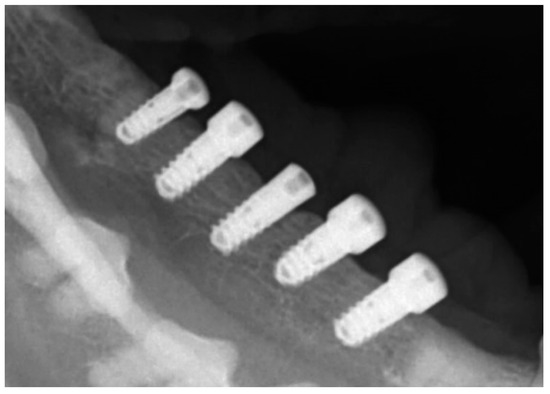

2.5. Radiological Follow-Up

To check the peri-implant vertical alveolar bone status on the right side of the lower jaw at baseline, a conventional dental X-rays was taken immediately after the titanium abutments were installed, 3 months post-implantation (Figure 5).

Figure 5. Radiological follow-up immediately after the abutment connection, revealing no post-implantation pre-exposure bone loss around the screws.